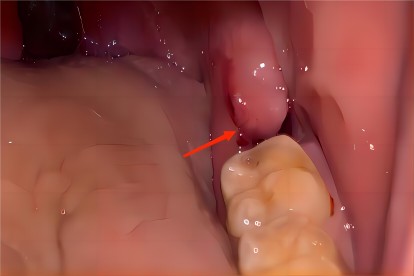

智齿是第三磨牙,可能会影响其他磨牙的正常生长,需要及时拔牙。拔牙后短期内牙龈会有窟窿,后期凹洞处会逐渐与正常牙龈持平。

【恢复过程】智齿拔牙后有一定恢复期,如果智齿生长混乱,需要切开牙龈,取出智齿后再缝合牙龈。智齿拔出后,原本的牙龈位置会出现一个窟窿,这是正常现象。随着时间的修复,拔牙后的窟窿会慢慢恢复,与正常牙龈高度持平,牙槽骨组织就会填满窟窿。